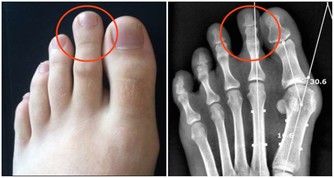

這是指太衝穴,位置在足背第一、二蹠骨結合部之前的凹陷中。